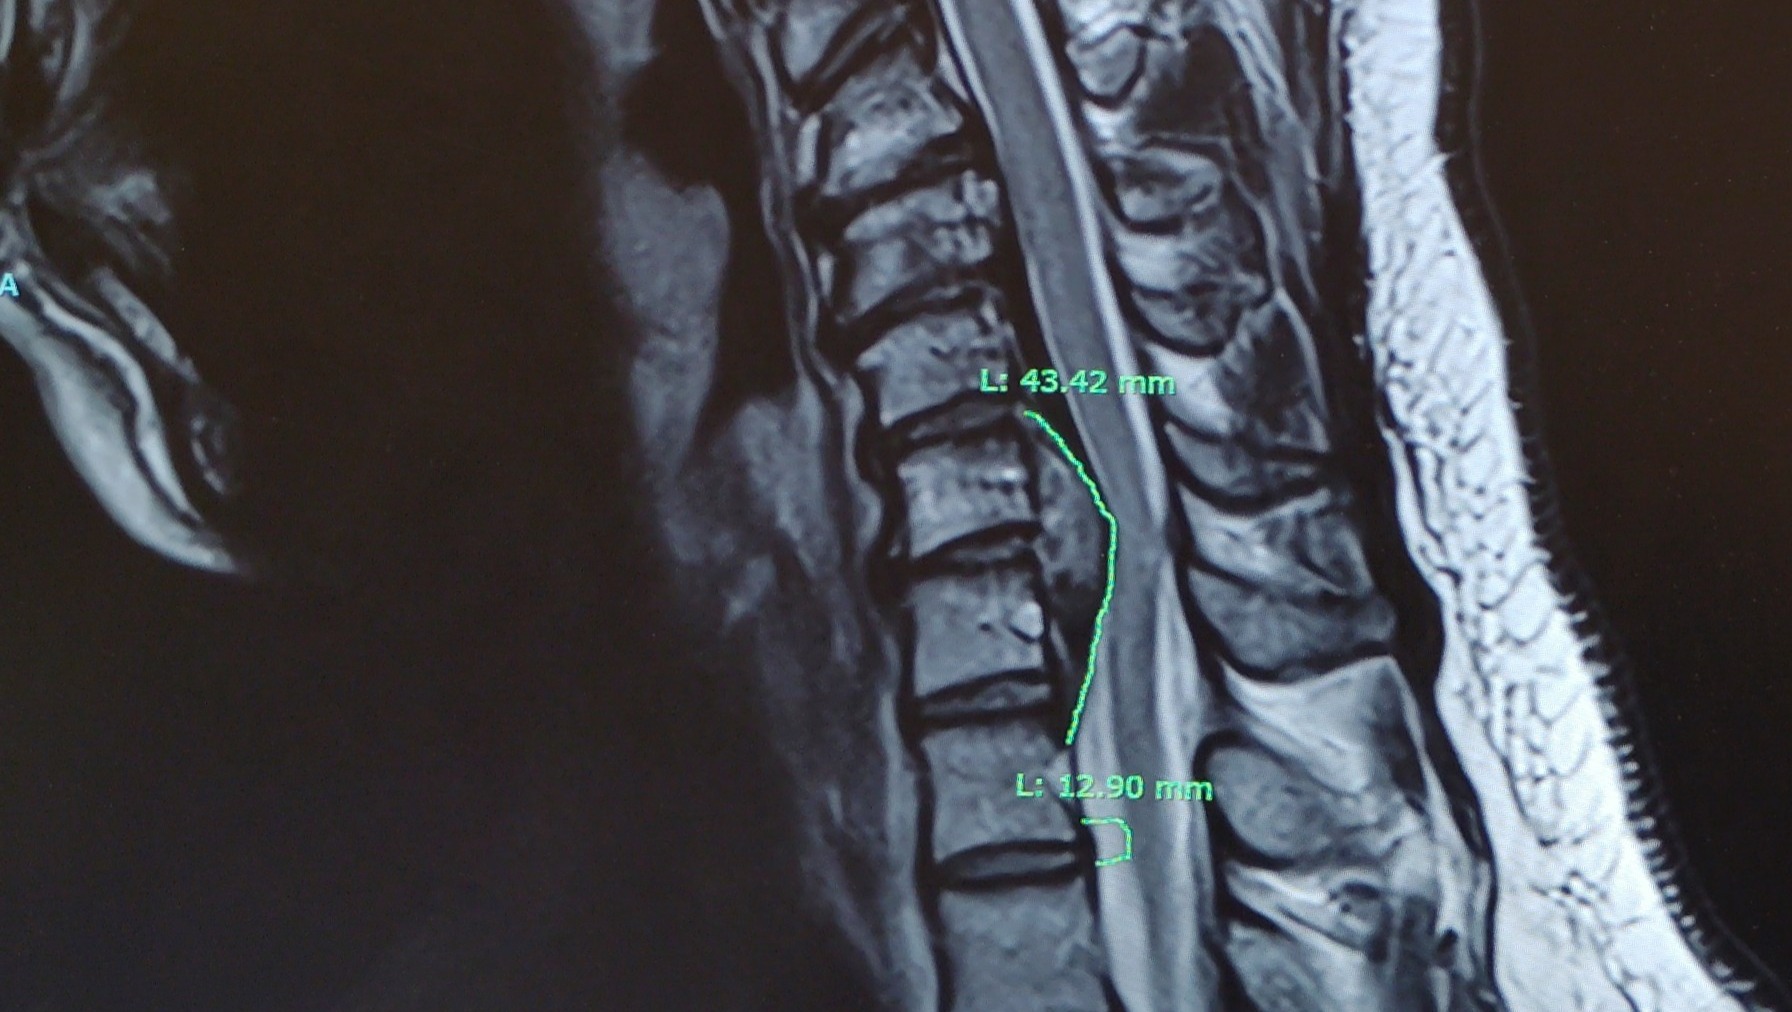

In August 2025, I was seriously injured while working. I was diagnosed with Cervical Radiculopathy & Cubital Tunnel Syndrome. Since that day, I have not been able to return to work. My injury is severe enough that I now have to undergo Anterior Cervical Spine surgery, and my doctors have made it very clear that recovery will take time.